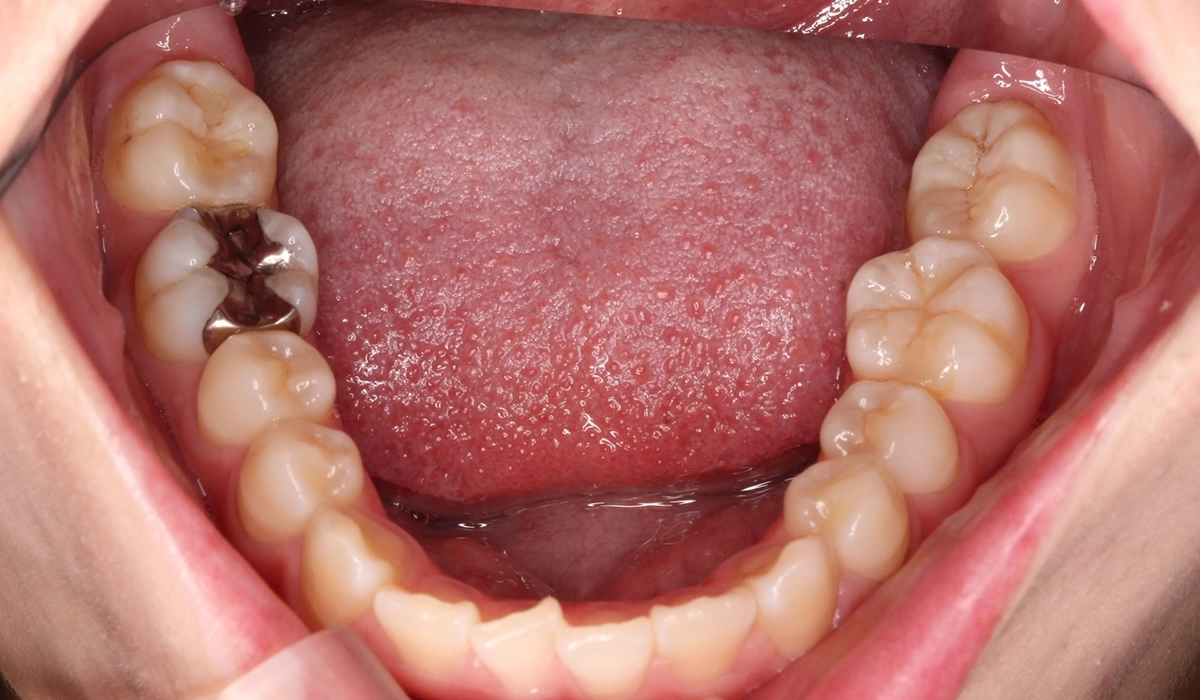

術前:下顎

術後:下顎